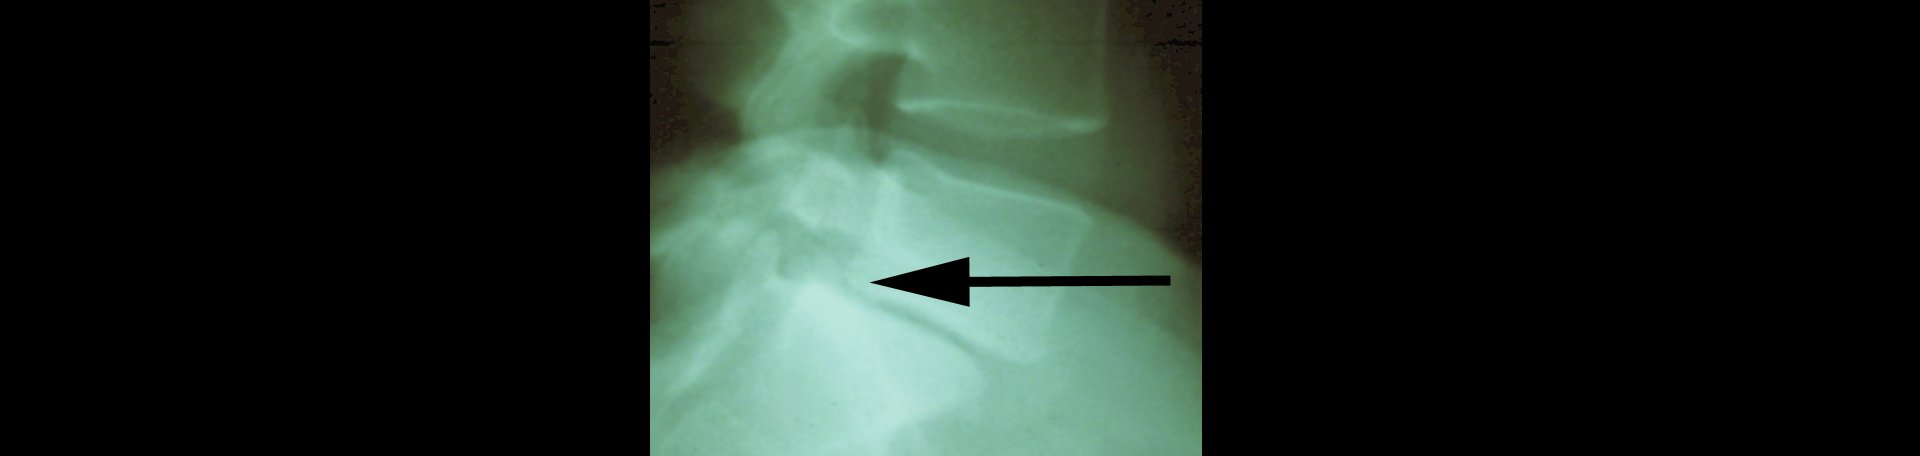

A spinal condition that occurs when one vertebral body (one of the spinal bones) slips forward or backward upon the vertebral body next to it resulting in back and/or leg pain, spondylolisthesis isn’t all that uncommon. About 20% of the adult population has it. Low back pain is its companion. Degenerative spondylolisthesis is most often seen at the L4/5 lumbar spine level in adulthood. Non-degenerative spondylolisthesis usually affects the L5/S1 level. (1) Researchers studied the natural history of degenerative spondylolisthesis and its related slippage by looking through published studies. They found that over 4 to 25 years, 12% to 20% acquired degenerative spondylolisthesis while 12%-34% of existing degenerative spondylolisthesis progressed. It is valuable to note that 2/3 of spondylolisthesis patients’ slips didn’t progress. (2) Non-progressing is good! Even degenerative is good as it often responds to care. Your Fort Wayne chiropractor is ready to help with Fort Wayne spondylolisthesis!